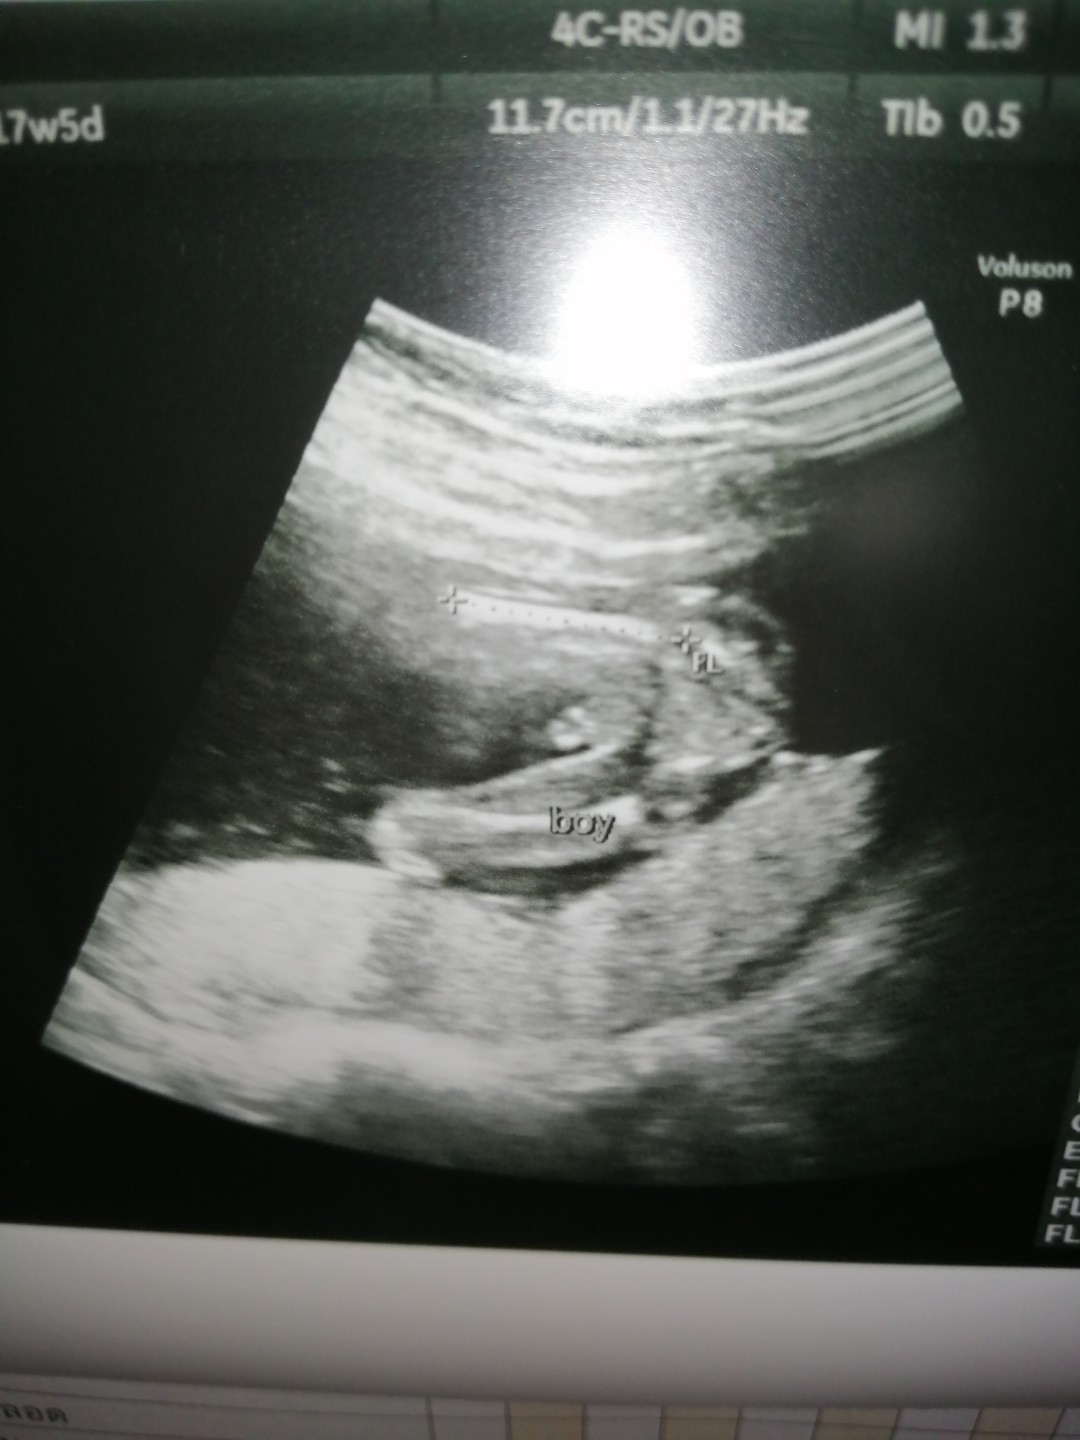

ตอน17+5ค่ะตอนนี้21+1

ผช..จร้า7ก.ค.